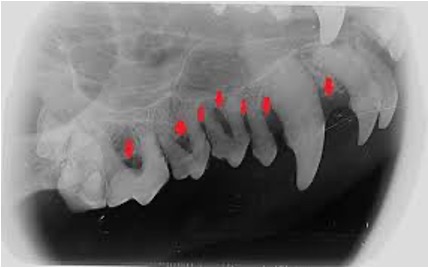

Diagnostic Standards as the Foundation of Effective Treatment